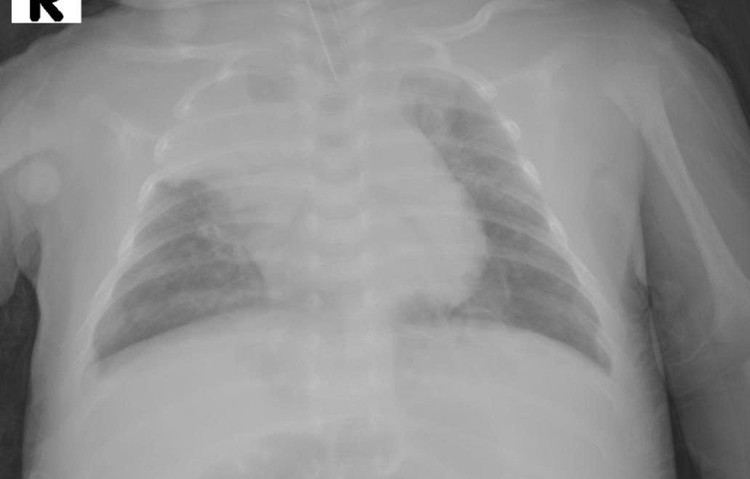

Trẻ bị viêm phổi, suy hô hấp tiến triển nặng - Ảnh BVCC

Trẻ nhi 32 ngày tuổi, nhập viện với chẩn đoán viêm phổi RSV (+), suy hô hấp. Tiền sử bé là trẻ đẻ non 36 tuần có cân nặng lúc sinh 2300gr. Ban đầu trẻ được hỗ trợ thở oxy, nhưng chỉ sau nửa ngày, tình trạng nhanh chóng xấu đi, buộc trẻ phải thở máy không xâm nhập (NCPAP).

Đến cuối ngày thứ 3, bé suy hô hấp nặng, phải đặt ống nội khí quản và thở máy xâm nhập. Tuy nhiên phổi giãn nở kém, tổn thương lan tỏa, khí máu ghi nhận pH 7,1 và pCO₂ 115 mmHg, cho thấy toan hô hấp nặng.